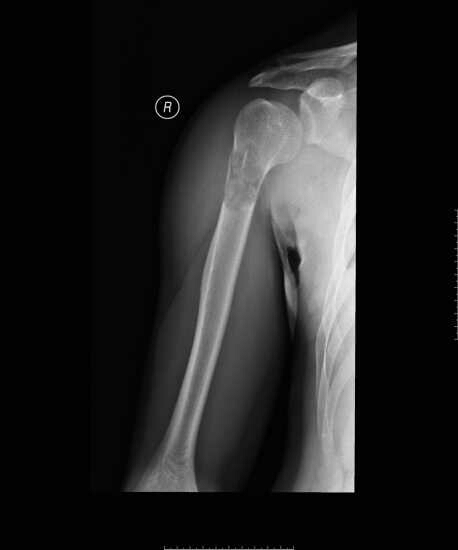

男,23岁,工人。

主 诉:轻微外伤后右上臂疼痛、肿胀伴活动受限1天。

现病史:1天前轻微外伤后出现右上臂疼痛,当时即出现右上肢活动受限。不愿主动活动右上肢。受伤以来,患者神志清,精神一般,睡眠及进食差,大小便正常。体重体力无明显变化。

检查及结果: T 36.5℃, P 72次/分,R 20次/分, BP141/84mmHg。右肱骨照片如下,病理性骨折基本可以肯定。

请大家着重讨论以下几个骨病鉴别:骨纤、骨囊肿、骨巨细胞瘤。